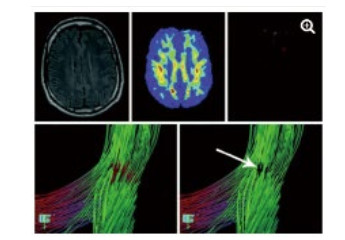

DWI利用梯度回旋技术来监测水分子弥散的难易程度,能比其他影像手段更早发现脑缺血。DTI是DWI的发展和深化, 结合FA等参数能独特显示全脑白质传导束,并且能够评估其功能的完整性。研究表明,重度脑外伤患者胼胝体膝部和压部的FA值下降,同时压部白质纤维束数量减少。这些变化不仅仅与GCS评分有关,还和患者的预后,包括认知评分显著相关[31-34]。借助DTI技术,能从形态学上解释意识障碍存在的结构基础,直观评价患者损伤程度[34](图 3)及预后[35],具有较高的精准性。在心搏骤停后昏迷患者意识评估研究中发现,DTI及FA的联合应用在预测患者预后不良的灵敏度达94%,特异度达100%[35]。

| 图 3 一例49岁TBI患者,常规MRI检查未发现明显异常(左上图)运用FA技术显示在左侧额叶白质中发现一个FA减少的区域(上中图),运用DTI显示局部纤维提示不联系(箭头所指) |